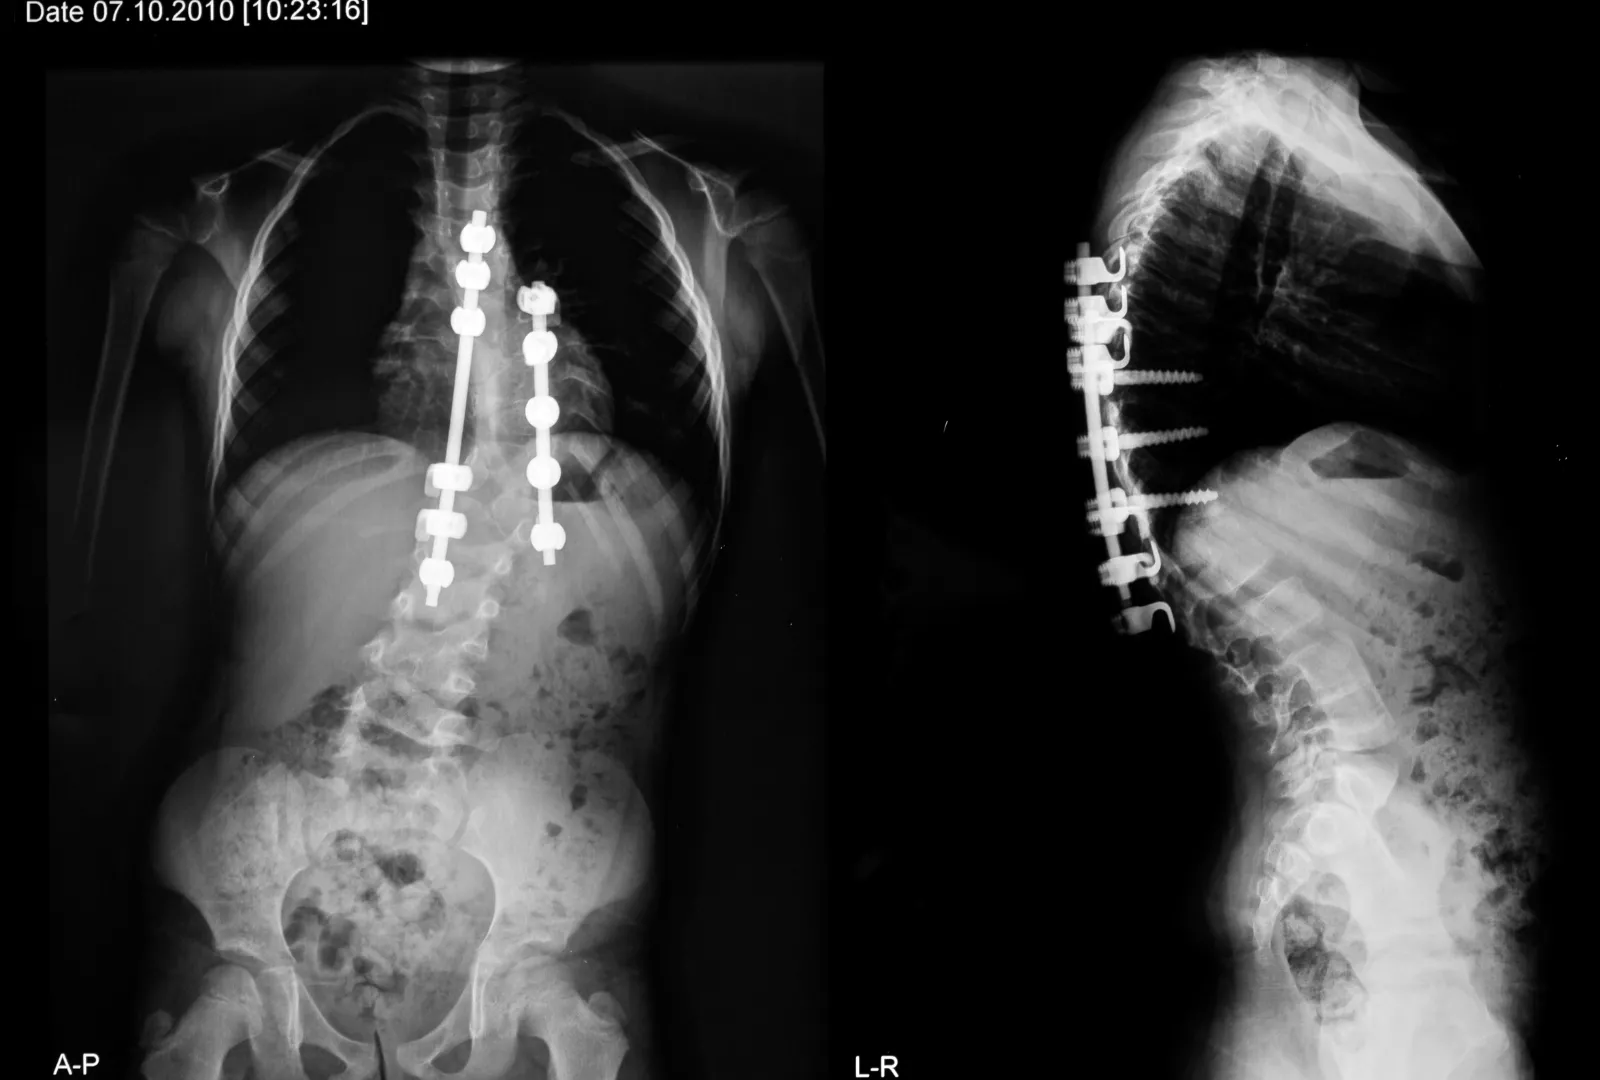

Although spinal surgery (scoliosis surgery) is not ruled out for the treatment of this scoliosis condition, it should be reserved only for extreme cases (abnormal curvatures over 40 degrees) as it always produces scar tissue which becomes semi-necrotised.